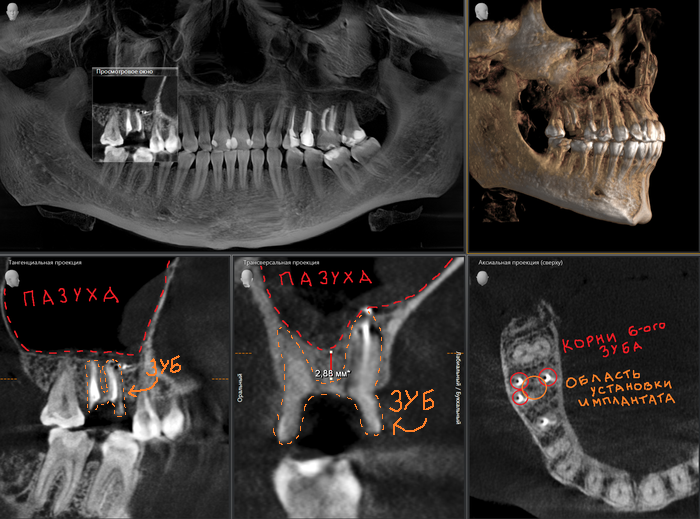

Помните, я говорил, что имплантат должен стоять по центру? Так вот 3-х корневой зуб не исключение. Имплантат устанавливается, как и в предыдущем случае, в перегородку, но уже трехкорневого зуба. Как мы видим высота кости в этой области около 3мм. Данного объема недостаточно для постановки имплантата оптимальной длины, следовательно объем нужно увеличивать. Манипуляцию проводят при помощи специального «костного материала». Кто-то называет его «костный порошок», не путать с «белым порошком», хотя он и белый, но представлен все-таки в виде гранул. Выпускается как просто в стеклянной таре,

Как мы видим условия в данном случае несколько хуже около 2мм. Но это не помешало нам провести операцию в полном объеме.